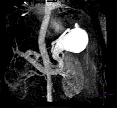

arteriovenous fistula - Splenic vein aneurysm. Splenic vein aneurysm.

Endovascular

management of incidentally discovered splenic arteriovenous fistula resulting from ruptured splenic aneurysm: Case report and review of the literature: Fig. 1. CT of the abdomen in arterial phase demonstrates fusiform arterial aneurysm (arrow) at the splenic hilum with intrasplenic tangle of vessels (arrowhead) (A). Figure (B) demonstrates dilated splenic vein (arrow).